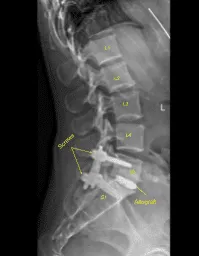

El autoinjerto morselizado seleccionado durante la descompresión, así como el aloinjerto morselizado, se canalizaban al interespacio con embudo y prensado, y luego el espaciador intersomal de titanio se tamponaba suavemente en el interespacio bajo guía fluoroscópica y se expandía hasta su posición correcta. La AP y la fluoroscopia lateral mostraron una posición adecuada.

A continuación, se realizó una tomografía computarizada adicional que mostró una posición ligeramente medial del alambre guía izquierdo de la L5. Por ello, se volvió a utilizar la navegación Jamshidi para volver a cenular el pedículo izquierdo L5 en una posición óptima. los tornillos pediculares canulados y navegados se colocaron sobre los cables K y se retiraron los cables K, con L5 y S1 a la izquierda logrando una instrumentación no segmentaria.

Las capas dérmicas se cerraron con suturas 2-0 de Vicryl. Las incisiones cutáneas se cerraron con suturas subcutáneas 4-0 de Monocryl, limpiadas, secadas de forma estéril y vendadas con pegamento Dermabond. El Dermabond también se aplicó para las incisiones de clavos de Schanz en la matriz de cresta ilíaca. Obtuvimos una tomografía computarizada final y radiografías finales que mostraron la posición correcta de todo el hardware.